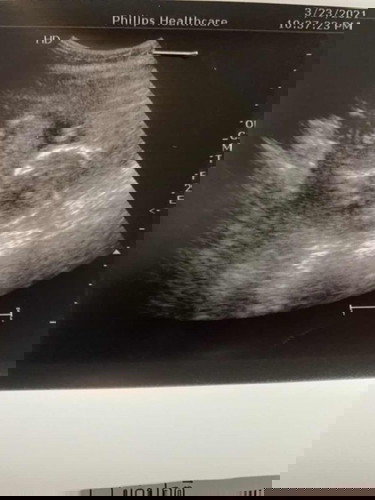

แม่ๆรู้เพศน้องตอนกี่วีคคะ

ตอนนี้น้อง16+6หมอบอกยังไม่รู้เพศเลย

12wค่ะ ตรวจนิฟ